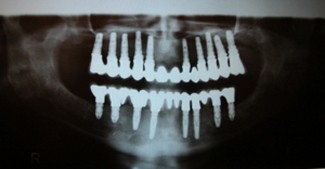

Fogbeültetés: röntgenkép implantátumos alsó-felső hídról